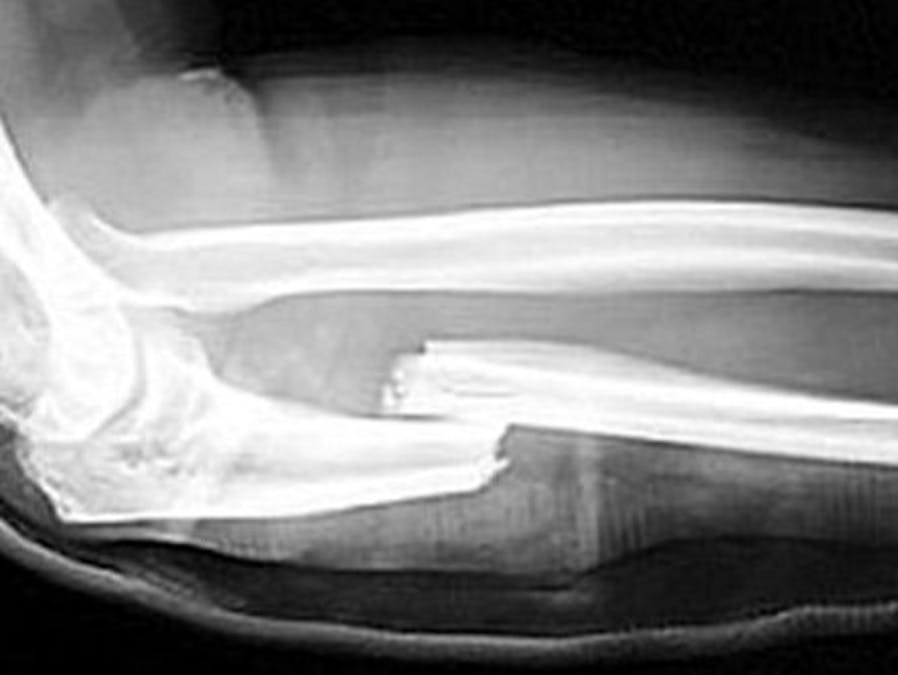

Using Walabot for detecting broken bones in extremities

Replace X-rays to check for broken bones with Walabot for portable and quick diagnosis in office or in the field.